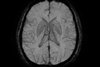

Identificação humana